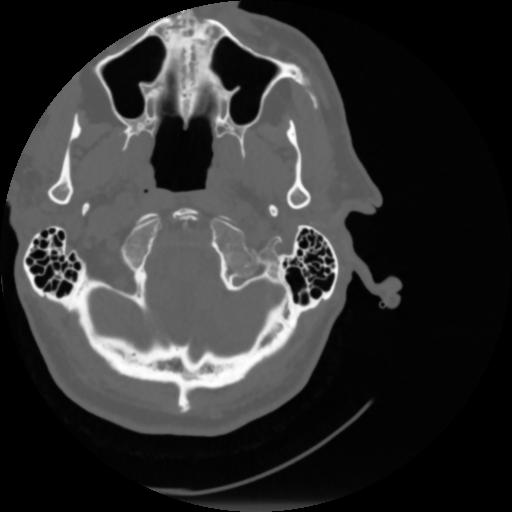

4 CEREBRO,,Vol,0.5,CEREBRO,,